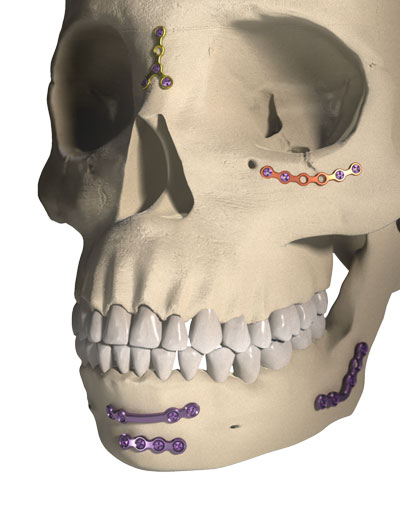

ORTRAUTEK est une gamme complète, dédiée à la chirurgie orthognathique, génioplastie, traumatologie et petite reconstruction.

Il s’agit d’un très large panel de vis et de plaques de différentes formes se déclinant dans des épaisseurs et des grades de titane distincts, le tout aisément identifiable grâce à un code couleur.